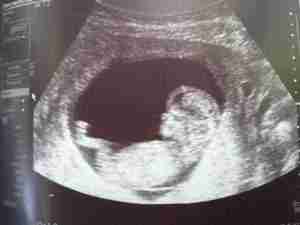

Ahora puedes leer el artículo de La Voz del Muro sobre La terrorífica ecografía de un bebé que se viralizó por las redes sociales.

Una madre australiana se llevó una sorpresa cuando vio por primera vez la imagen de su hijo

Una joven madre australiana estaba muy emocionada por tener las primeras imágenes de su bebé. Ya en el consultorio, la mujer miraba atenta la pantalla del ultrasonido, que…